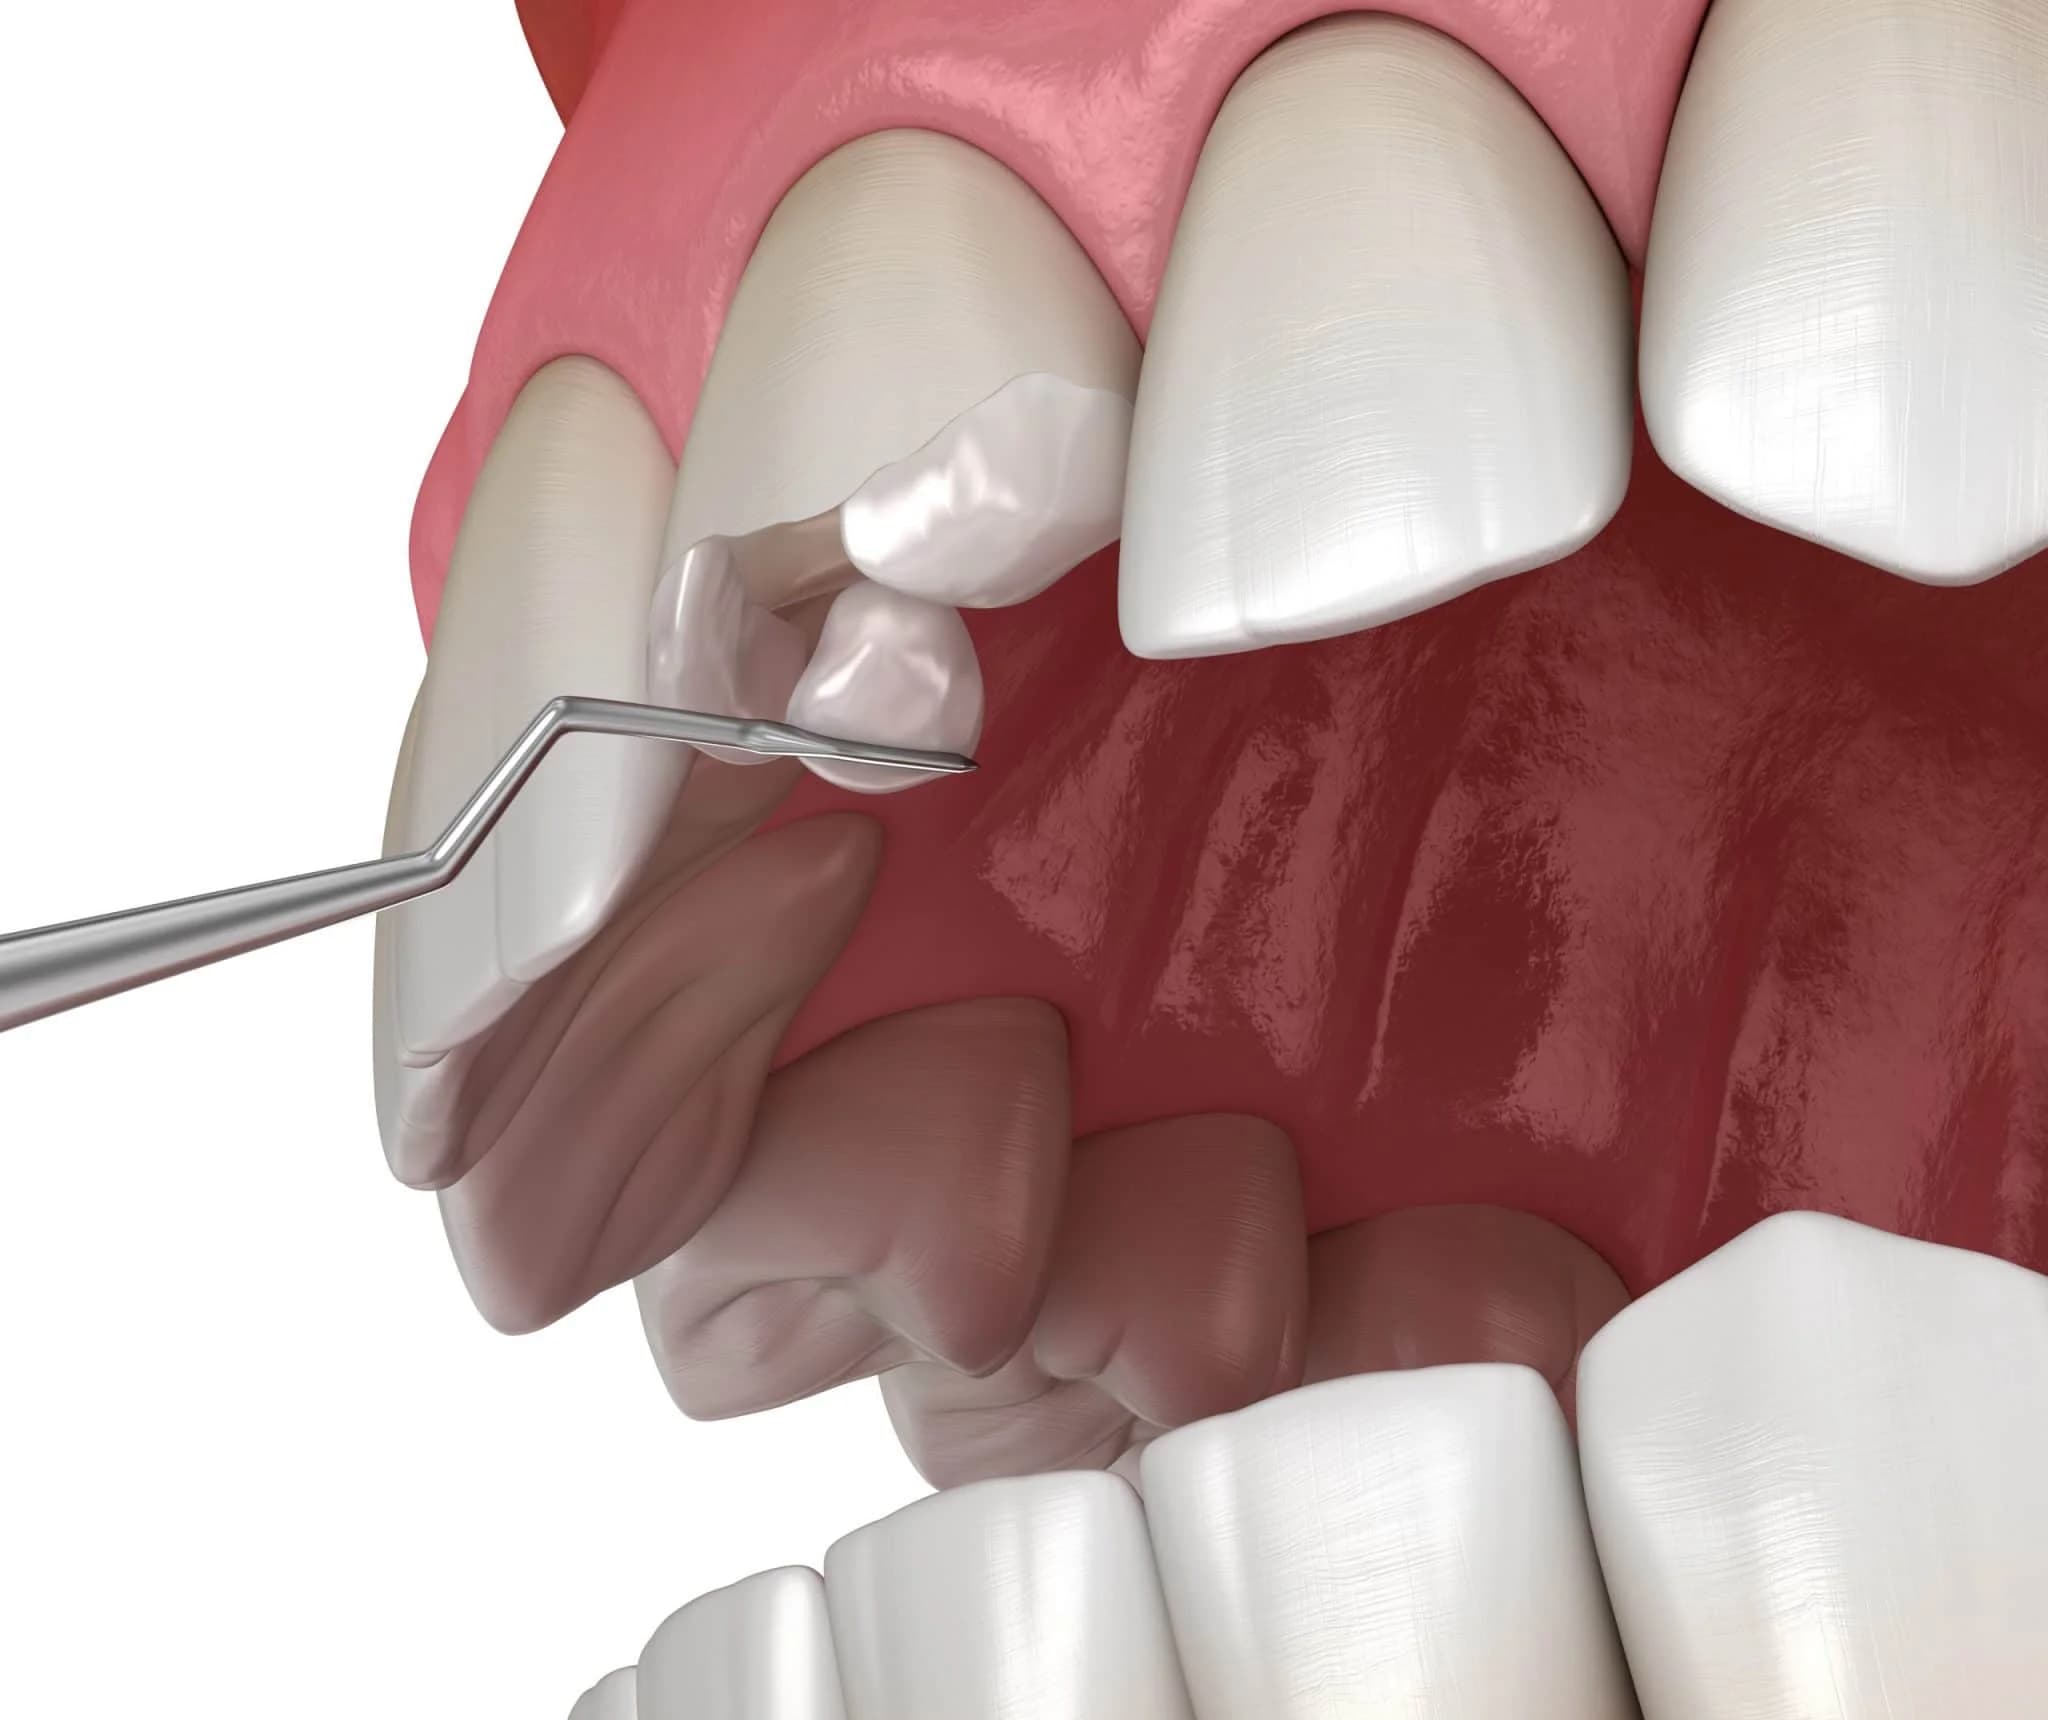

Inlays and Onlays

If the size of your cavity is too big for a filling and too small for a crown, then an inlay or onlay may be used. These custom restorations fit into your natural tooth structure like puzzle pieces and are bonded into place. While an inlay fills the area between the cusps of your teeth, an onlay also covers at least one cusp.